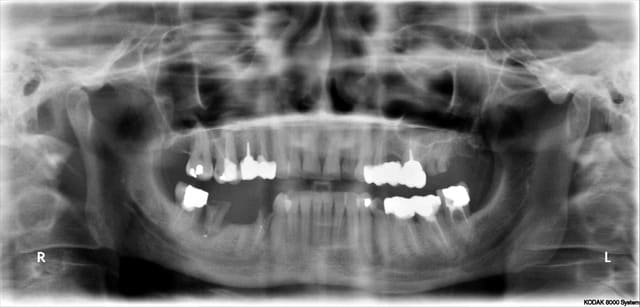

Le cas de ce matin, cela montre que même avec une planif et un guide c'est le temps opératoire qui décide

j'ai bêtement cassé la table vesti de la 45 lors de l'exo

par sécurité je suis allé chercher un meilleur ancrage en distal,

Donc le guide ne fait pas tout!!!